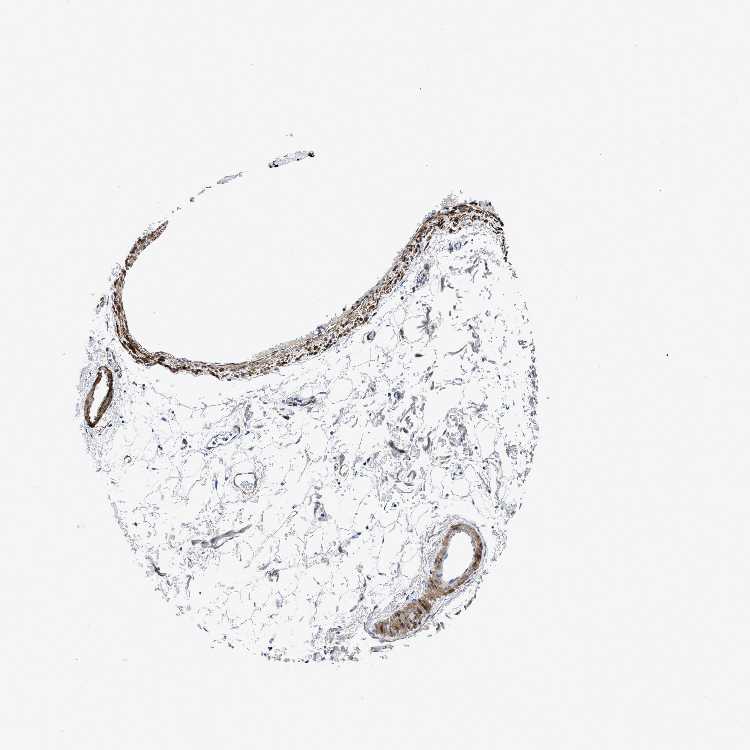

ADIPOSE TISSUE - Antibody stainingi

Antibody staining in the annotated cell types in the current human tissue is reported as not detected, low, medium, or high, based on conventional immunohistochemistry profiling in selected tissues. This score is based on the combination of the staining intensity and fraction of stained cells.

Each image is clickable and will lead to virtual microscopy that enables deeper exploration of all samples and also displays staining intensity scores, fraction scores and subcellular localization as well as patient and tissue information for each sample.

Antibody HPA016631

Adipocytes Not detected